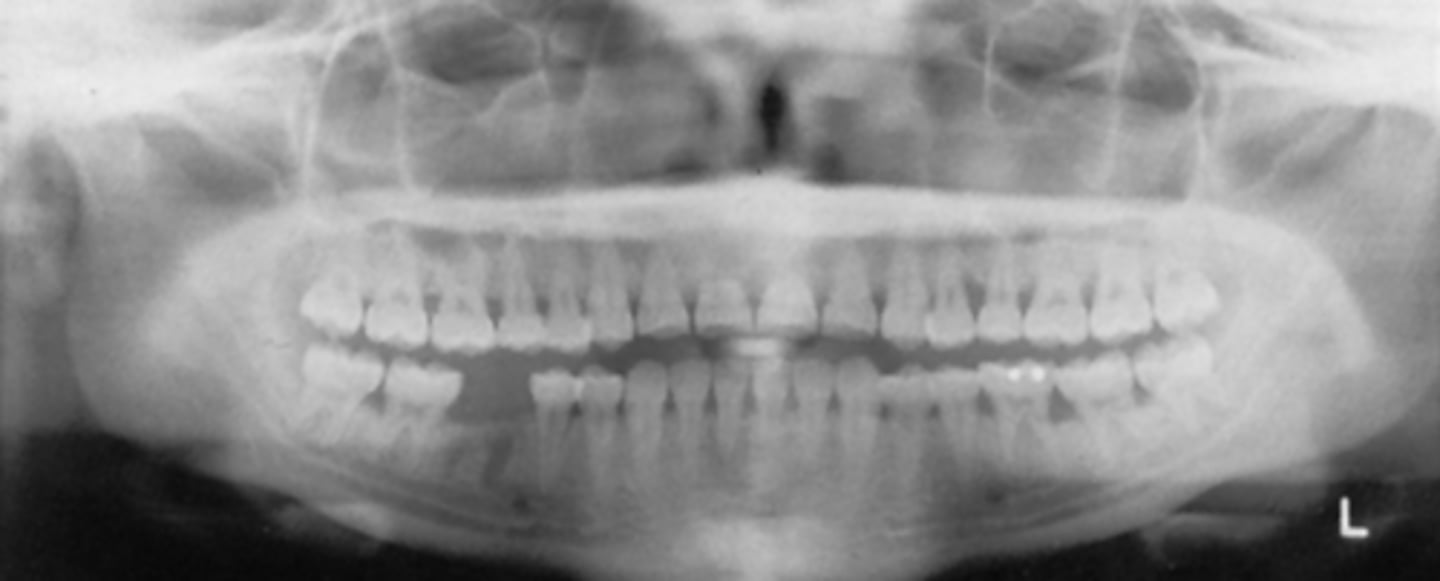

A) in front

In this image, the teeth are ___ the groove of the bitestick

A) in front of

B) behind